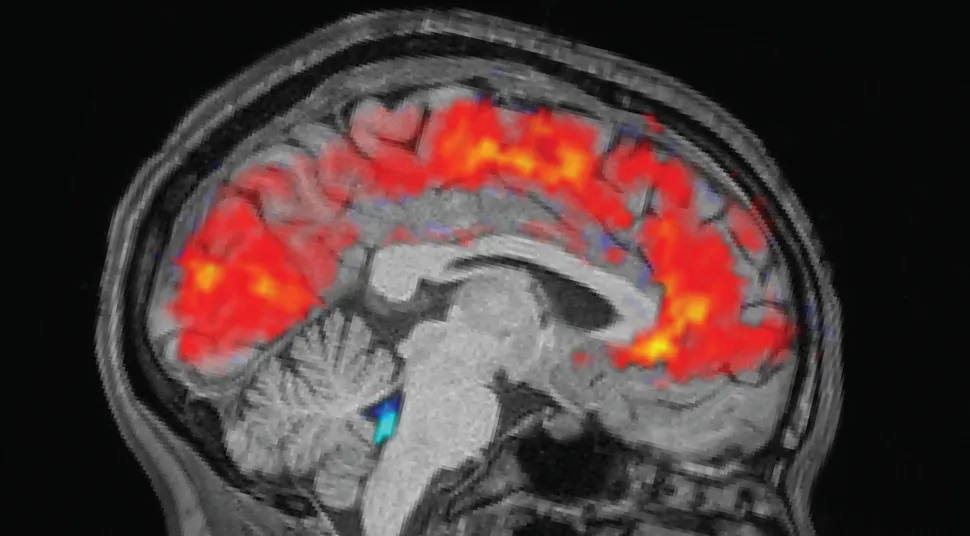

مغز هنگام خستگی شدید وارد حالتی شبیه به خواب میشود

جریان خون و مایع مغزیــنخاعی در مغز هنگام بیخوابی به همان شیوهای تغییر میکند که معمولا فقط در «خواب عمیق و آرام» دیده میشود.

به گزارش مجله زیبایی سبز به نقل از ایندپندنت از لایوساینس، بر اساس مطالعهای که ۲۹ اکتبر در مجله «طبیعت علوم اعصاب» (Nature Neuroscience) منتشر شد، وقتی پس از یک شب کلا نخوابیدن، حواستان ناگهان پرت میشود یا تمرکز ندارید، در واقع مغز دارد مایع مغزینخاعی (CSF) را که اطراف مغز و نخاع را احاطه میکند و بخشی از سازوکار دفع مواد زائد از مغز است، از خود بیرون میراند و تمرکز هنگامی بازمیگردد که این مایع دوباره به مغز برمیگردد.

طبق انتظار، افراد در حالت خستگی دیرتر محرکها را تشخیص دادند و تعداد بیشتری از نشانهها را از دست دادند، اما آنچه محققان شگفتزده کرد، این بود که در مغز افراد خسته، جریانهای شدید و ناگهانی (پالس) مایع مغزینخاعی را مشاهده کردند؛ این حالت با آهسته شدن امواج مغزی همراه بود؛ یعنی همان نوع فعالیت مغزی که معمولا وقتی وارد خواب عمیق غیر REM میشویم، دیده میشود. لوئیس توضیح داد: «تا حالا چنین الگوهایی را فقط هنگام خواب دیده بودیم، نه در فردی که بیدار است.»